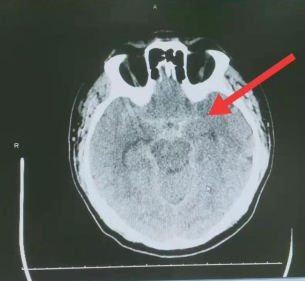

患者,男性,58岁,因“剧烈头痛80分钟”入院。查体后患者意识清、脑膜刺激征阳性、四肢活动正常,Hunt-Hess分级 2级。术前CT考虑后循环动脉瘤破裂可能性大,急诊行全脑血管造影后,神经外二科副主任医师王庆历为其实施支架辅助动脉瘤栓塞术。

术前CT